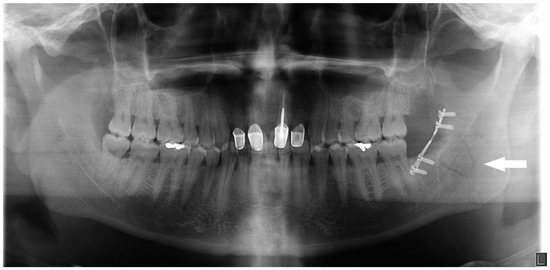

Computed tomography (CT) of the face was positive for a minimally displaced fracture of the left mandibular angle that was continuous with the periodontal ligament space of an erupted nonfunctional lower left third molar (Figure 1a–d). Inaddition to left mandibular angle fracture, the radiologist noted left-sided soft-tissue fullness that was thought to represent a possible hematoma that was 3.4 × 5.5 cm (Figure 2).

Figure 1. (a) Preoperative orthopanorex showing fracture of left mandibular angle with communication to the periodontal ligament space tooth no. 17. (b) Axial view on CT scan showing left mandibular angle fracture. (c) Coronal view on CT scan showing left mandibular angle fracture.